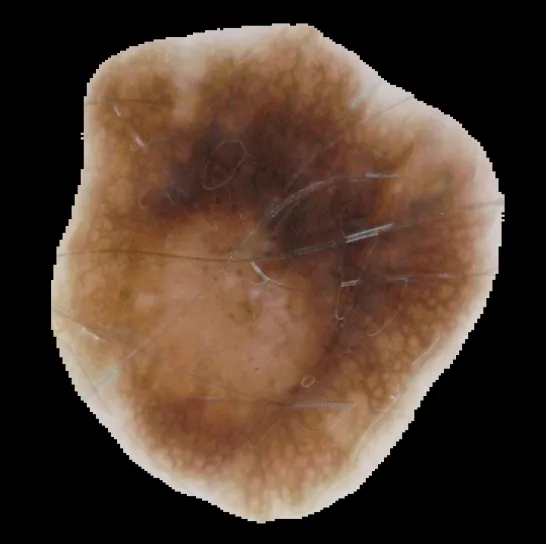

This project implements a deep learning model for skin lesion segmentation using a UNet architecture. The model is developed in PyTorch and deployed with an interactive Streamlit application, allowing users to upload skin lesion images and view segmentation results in real-time.